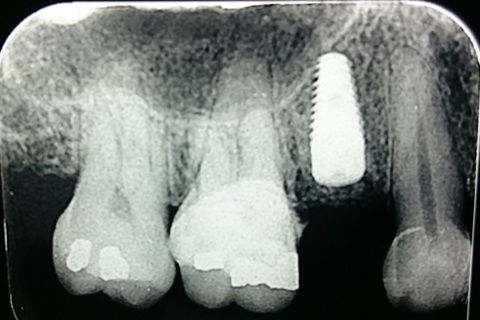

Radiografia 15 dias após implantação

Radiografia 5 meses após implantação

Paciente sexo feminino,aproximadamente 40 anos, encaminhada pelo protesista para exodontia do elemento 14 e implantação. O mesmo verificou trinca na raíz do elemento 14. Após documentação e paciente avaliado o tratamento de opção em comum acordo com a paciente foi , exodontia, implante imediato com ROG (alobone) e enxerto gengival livre para ocluir o alvéolo, com provisório tipo aleta e função tardia. (Caso em andamento).